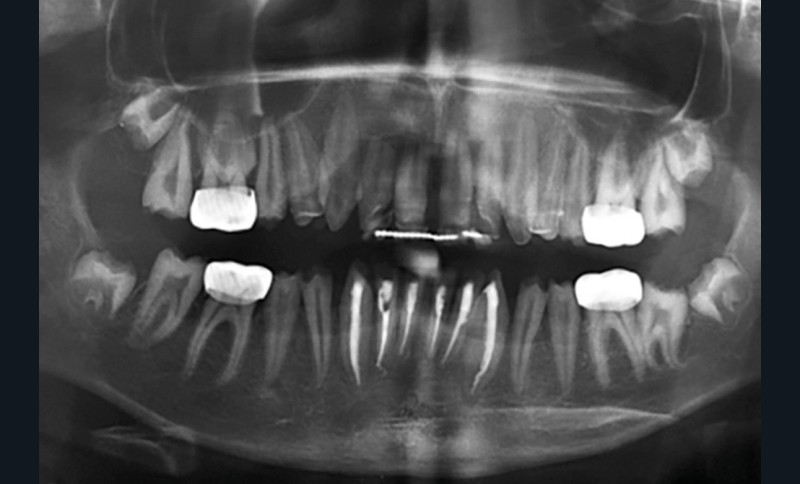

Une patiente âgée de 12 ans a été adressée au cabinet pour « une prise en charge complète sur le long terme » par son praticien traitant. Elle était accompagnée par sa mère. Elle présentait des couronnes transitoires en résine sur le secteur incisivo-canin au maxillaire ainsi que les premières prémolaires, des coiffes pédodontiques métalliques sur les premières molaires, une absence totale d’émail sur l’ensemble de la denture, à l’exclusion des bords libres des incisives mandibulaires (fig. 1 à 3). Le bloc incisivo-canin mandibulaire avait bénéficié de traitements radiculaires (fig. 4). Les incisives maxillaires présentaient des rhizalyses d’une importance significative (fig. 5 et 6). La patiente se plaignait d’hypersensibilités à la mastication et au brossage, la demande esthétique était forte.